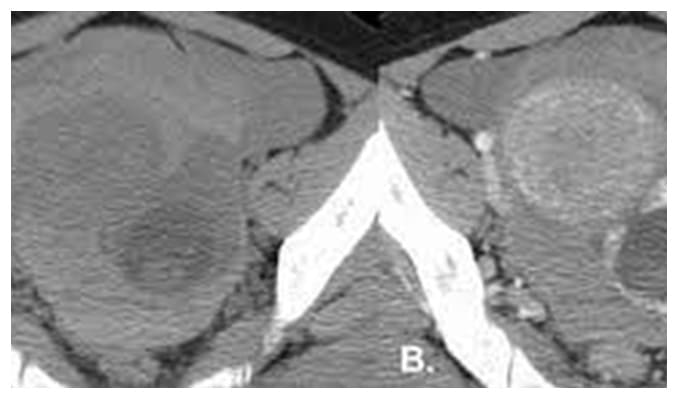

Una de las principales herramientas con las que contamos los ginecologos hoy en dia para detectar los miomas, además del historial de hemorragia menstrual y de dolor, que algunas pacientes pueden presentar, esta el ultrasonido que de rutina se realiza en el consultorio, ya que muchas veces los miomas son asintomáticos.

También se pueden usar estudios como la tomografía o la resonancia sin embargo el ultrasonido tiene una efectividad diagnostica en médicos con experiencia cerca del 100%.